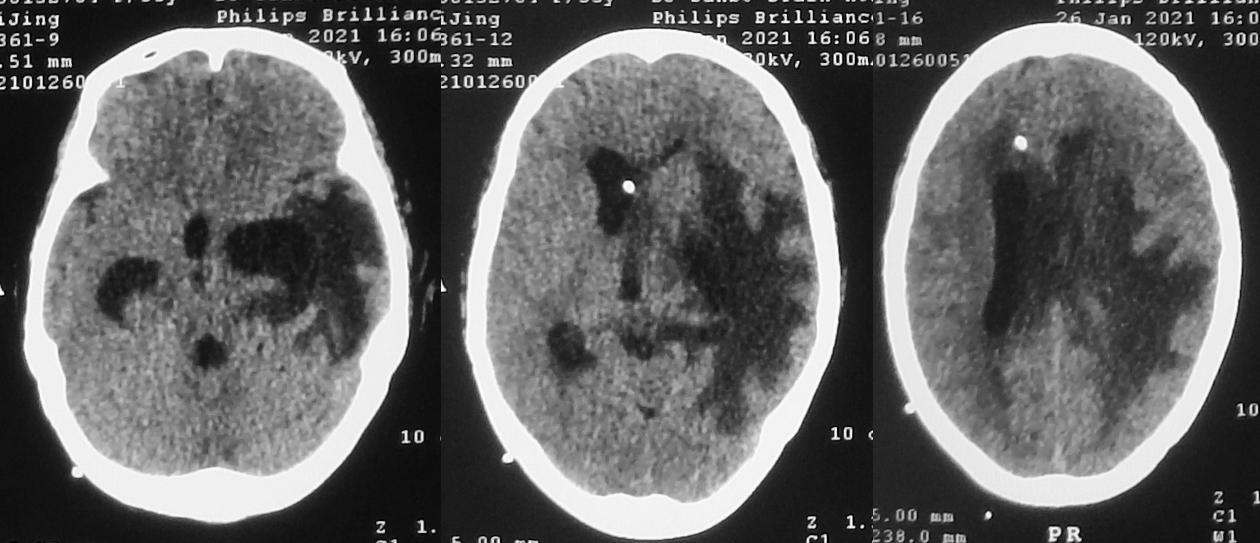

但发病后77天,即脑脓肿清除术后第48天,脑室腹腔分流术后第12天,即2021年1月25日,患者出现精神变差,同时呕吐1次。复查头颅CT较前(2021年1月19日)无明显变化( 图-26 )。

图-26: 2021年1月25日头CT

次日,即2021年1月26日,患者精神仍差,反应迟钝,呕吐2次。复查头颅CT见左侧脑室颞角稍扩张( 图-27 )。

图-27: 2021年1月26日头CT

当天,即发病后78天,即脑脓肿清除术后第49天,脑室腹腔分流术后第13天,即2021年1月26日,行第3次左侧颞角外引流术。但术后患者意识无明显改善。2021年1月28日患者再次出现发热,体温38.4℃,反应迟钝,复查头颅CT见左侧脑室颞角缩小,但右侧脑室较前扩张( 图-28 )。第3次左侧脑室颞角引流后脑脊液细菌培养回报为表皮葡萄球菌。给予抗炎治疗。

图-28: 2021年1月28日头CT